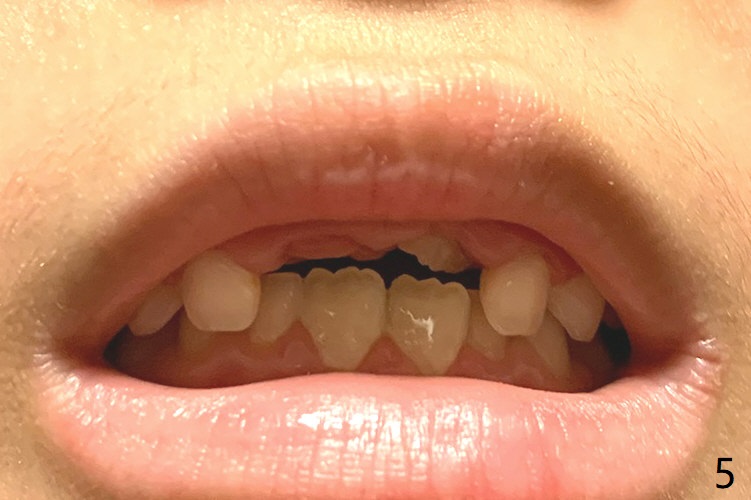

6岁11月女上乳中切牙松动许久,但不脱落,根尖片显示正中多生牙(图一:M),CT显示后者位于腭侧(图二:P)。Take preop photos to show whether the lower lateral incisors have erupted or not. If yes, remove the upperdeciduous central incisors. 一个月后病人回来时,右上乳中切牙已脱落,左上松动 ,术中后者好像影响视野而拔除,腭侧切口,暴露左上1后,拔除多生牙(图三)。 术后3个星期左上中切牙萌出,扭转,反合(图四,五)。术后六个月仍旧如此(图六,七),右上中切牙未萌出,小孩害怕促进萌出手术。准备制作活动矫正器。